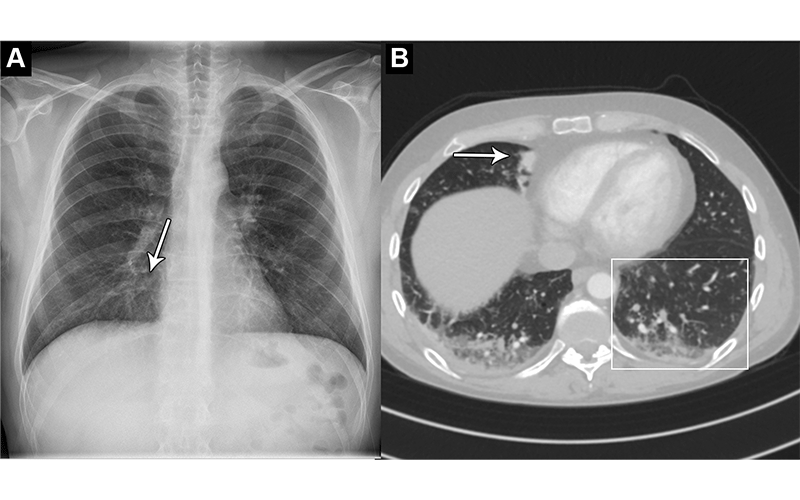

Images in a 44-year-old man who presented with chest pain and dyspnea. (A) Chest X-ray shows very subtle nodular opacities, primarily in lower lobes, representative of pneumonia and a discrete silhouette sign of the right cardiac border (arrow). The AI system interpreted this chest X-ray as normal. It was also interpreted as normal in the clinical radiology report. (B) CT scan shows the lower lobe airspace opacities with vague tree-in-bud morphology (box) and an area of consolidation (arrow). Pulmonary angiography was performed 5 hours after X-ray. This was the sole false-negative “critical” finding by the AI tool.